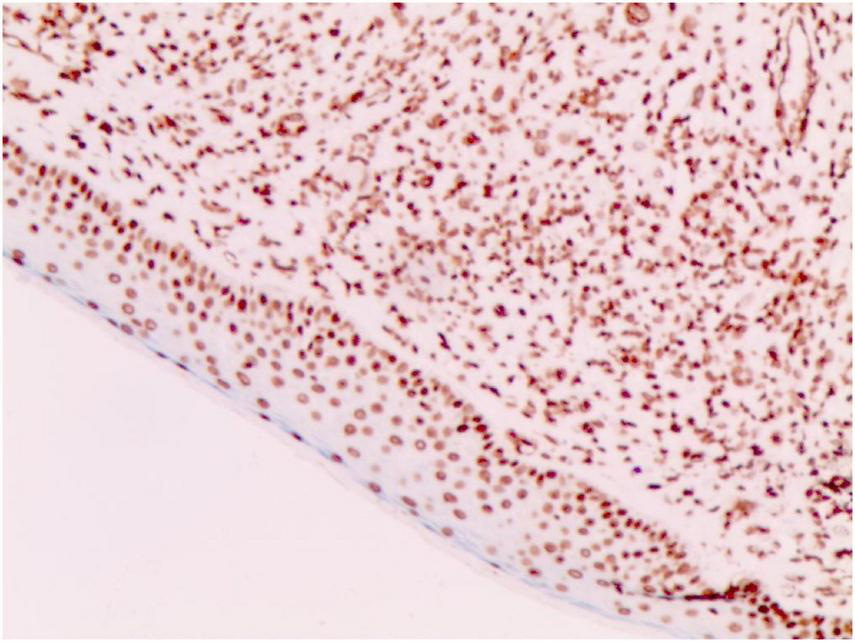

FIGURE 4

S-100 (+) (Immunohistochemical staining, × 200).

No abnormalities were found upon routine blood and urine tests, coagulation function test and syphilis/HIV screening. Chest X-ray and abdominal B-ultrasound also revealed no abnormalities. Cutaneous histopathology: epidermal processes disappeared, and the dermis was diffusely infiltrated by substantial tumor cells that were in the nested or clumpy form. These polygonal tumor cells were round or oval, which had abundant cytoplasm filled with eosinophilic granules, and were stained pale pink. The cellular nuclei were small, hyperchromatic and centered, with few mitotic figures, and multiple nuclei were observed in some tumor cells. Immunohistochemistry: S-100 (+), CD56 (−), NSE (−), vimentin (+), CD68 (+), Ki-67 (+), cell proportion: 5%, p53 (−), SAM (+−). CK (−), calponin (−), CD163 (−), desmin (−), CD34 (−), CD45 (−), CD30 (−), SMA (1A4) (−), ALK (−), HMB45 (−), melan-A (−).

2.3.3 The immunohistochemical results

S-100 (+), vimentin (+), CD68 (+), Ki-67 (+), cell proportion: 5%, SAM (+ −). Immunohistochemistry rules out melanoma, tumors of lymphoid origin, smooth muscle tumors, keratoacanthoma, SCC, xanthoma, and dermatofibroma, etc.